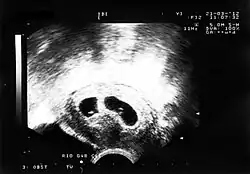

Sonogramm eineiiger menschlicher Zwillinge (4. Woche p.c.) – es zeigt dichoriale Zwillinge, die weder Chorion noch Amnion gemeinsam haben.